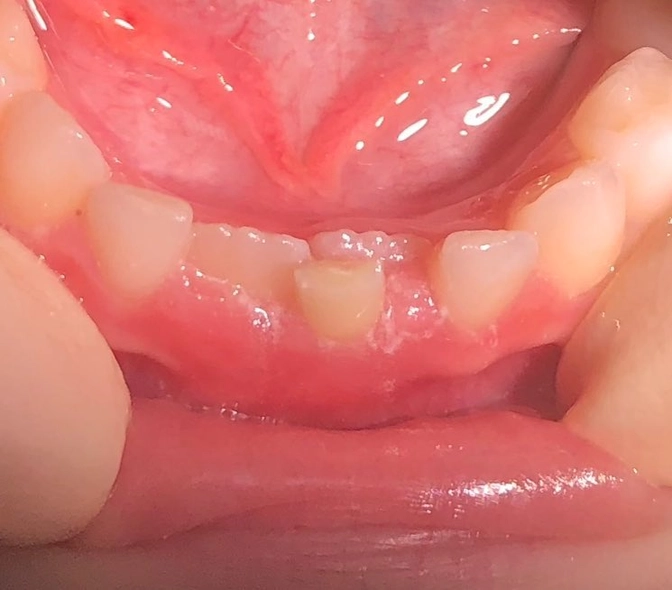

Зубы"в два ряда"?

Девочке почти 7..

А иногда бывает: постоянные уже прорезались, а молочные не в курсе, что пора и честь знать.

И стоят себе, никого не трогают, как на фото.

Волнистые края постоянных зубов видите?

Они у всех такие.

Со временем станут ровными.

Постоянные зубы не в зубном ряду.

После удаления рекомендовала маме производить легкие массажные движения, выдвигая зубы в правильное положение.

Языком тоже можно выталкивать.

Очень скоро зубы должны занять более правильное положение.